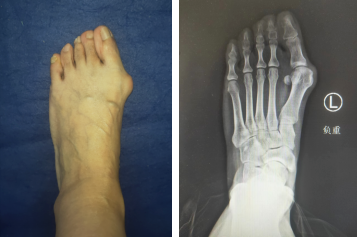

拇外翻,顾名思义就是大拇趾向外撇,而根部向内收,从而在根部长出一个大鼓包,前脚看起来像三角形的“大蛇头”。

在医学上也被称为拇囊畸形,即:第一跖骨内翻+拇指外翻。外翻角度通常大于15°,且常常伴有扁平足。是临床上的常见足病,国内发病率约5-10%,其中,女性发病率大于男性,并且多发于中老年妇女。

等到摄片结果出来,更是印证了曹主任的诊断。

黄阿姨的拇外翻已经到中度,并且严重的拇囊炎侵犯到跖趾关节,随着时间的推移,畸形会逐渐加重,需要进行手术治疗。这种手术在betway在线登陆仅需2个小切口就能解决侵扰黄阿姨十年的问题。